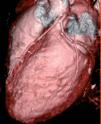

Se muestran las imágenes del árbol coronario que permiten descartar anomalías en esta localización. La figura 1 muestra una proyección axial de máxima intensidad (MIP) de la salida de las arterias coronarias. La figura 2 es una proyección coronal de máxima intensidad (MIP) de la arteria coronaria derecha similar a la proyección oblicua anterior derecha de la angiografía. Las figuras 3 y 4 son reconstrucciones en volume rendering en proyección oblicua anterior izquierda del tronco coronario izquierdo y su bifurcación y de la base del corazón, en la que se visualiza la salida del tronco coronario izquierdo. Se han retirado las venas pulmonares izquierdas. En la estación de trabajo, mediante el análisis avanzado de vasos se puede visualizar un vaso tortuoso o de trayecto curvo en un solo plano tomográfico permitiendo una cuantificación de la lesiones estenóticas. El estudio no detectó anomalía en la anatomía ni estenosis coronaria significativa en el paciente.

Figura 4. Reconstrucción en volume rendering de la base del corazón visualizándose la salida del tronco coronario izquierdo. Se han retirado las venas pulmonares izquierdas.